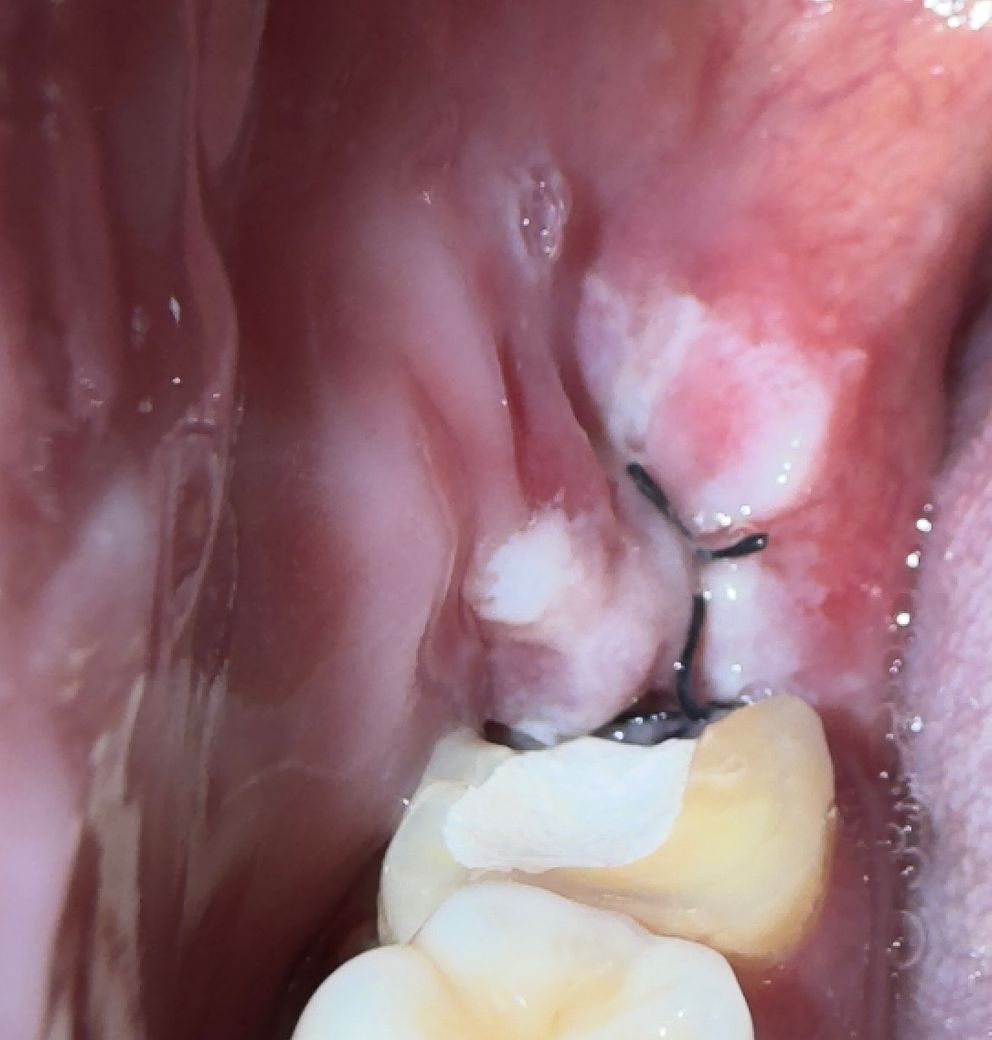

사랑니 발치 후 40시간 경과 염증인가요?

오른쪽 하악 매복사랑니 발치 후 40시간 지났습니다

통증은 없지만 약간의 열감과 붓기는 있습니다.

• 1번 째 사진

사진에 보이는건 염증이 잇어 보이진 않습니다 잇몸이 아물면서 생기는 자연스러운 현상이니 걱정하지 않으셔도 될것같습니다.

지금 사진으로 봐서는 특별히 드라이소켓의 가능성이나 치유부전의 가능성은 높지 않아 보입니다.

사진으로 봤을 경우에는 크게 문제가 있어 보이진 않습니다. 발칠 나고 나면 발췌한 부위가 자극이 되지 않도록 하는 것이 좋습니다. 발췌한 부위가 자극이 되면 출혈이 되고 치유가 늦어질 수 있기 때문입니다.

염증보다는 붓기만 있는 것 같습니다. 신경치료와 같이 진행한다고 문제가 되지는 않습니다.